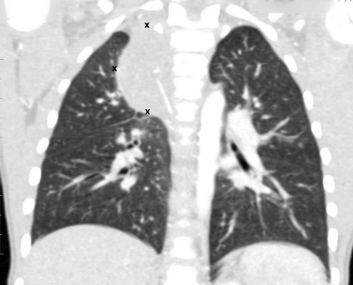

Очаговые изменения на КТ легких, подозрительные на туберкулезное поражение (выделено красным)

Туберкулез поражает пациентов любого возраста и пола, легкие вовлекаются в процесс наиболее часто. Болезнь считают социально опасной, так как при несвоевременной диагностике открытой формы (выделение микобактерий в окружающую среду при кашле) высок риск инфицирования окружающих людей. КТ органов грудной клетки при туберкулезе назначают в следующих ситуациях: